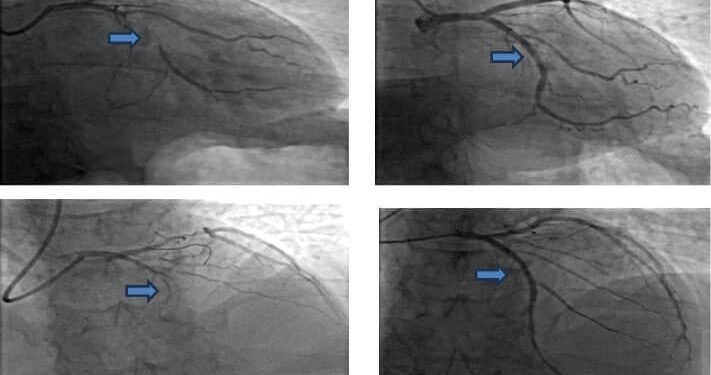

Ekip bác sĩ tại Khoa Cấp cứu đã nhanh chóng phối hợp cùng với Khoa Tim mạch Can thiệp tiến hành kịp thời hồi sức tim phổi cho bệnh nhân và ghi nhận bệnh nhân nhồi máu cơ tim cấp rất nặng. Sau hồi sinh tim phổi, bệnh nhân được duy trì huyết động với thuốc vận mạch liều cao, giúp thở qua ống nội khí quản. Tiến hành hội chẩn với ekip can thiệp mạch vành, khẩn trương vừa bóp bóng vừa chụp và can thiệp mạch vành cấp cứu. Kết quả chụp mạch vành cho thấy tắc hoàn toàn hai nhánh động mạch vành phía bên trái và tiến hành tái thông khẩn trương hai nhánh mạch vành bị tắc. Sau can thiệp, huyết áp phụ thuộc vận mạch, có nhịp tự thở, tri giác cải thiện dần. Sau 1 tiếng, bệnh nhân được rút ống nội khí quản và hỗ trợ thở bằng oxy mask có túi dự trữ. Sau 12 tiếng, bệnh nhân được ngưng thuốc vận mạch và tỉnh táo hoàn toàn. Bệnh nhân được điều trị nội khoa tối ưu sau nhồi máu cơ tim cấp và được xuất viện sau 5 ngày.